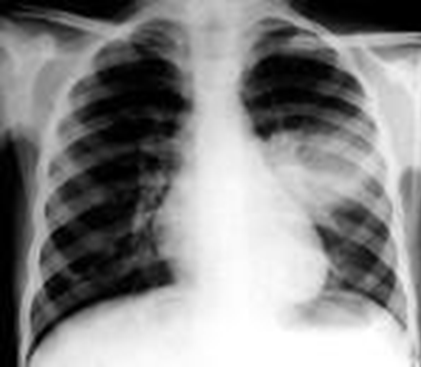

Further evaluation includes a complete blood count and differential and platelet count, long bone radiographs, and CSF analysis for VDRL, cell count, and protein. A positive CSF VDRL test, elevated CSF protein, and/or elevated CSF white blood cell (WBC) count without other causes may be due to congenital syphilis. Other tests should be performed as clinically indicated (e.g., chest radiograph, liver-function tests, cranial ultrasound, ophthalmologic examination, auditory brainstem response).